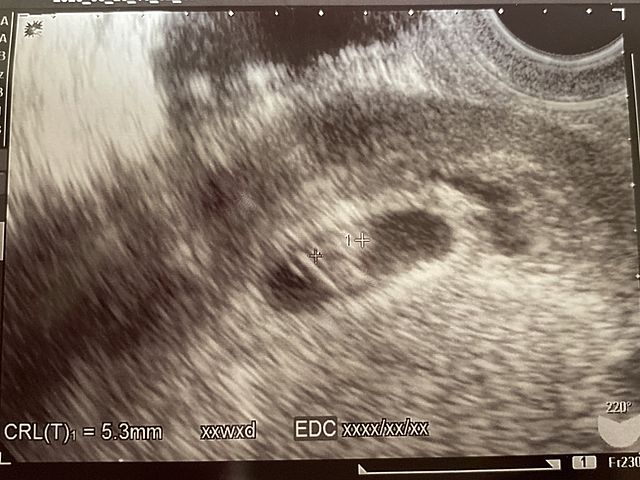

行ってきました!産婦人科![]()

心拍は‥

確認できました![]()

お腹に‥

赤ちゃんがいます![]()

2週間経ったから少しは大きくなってるかと思ったら‥

まだまだ小さかった‥

予定日が出せない大きさ(笑)

なので、また2週間後に行くことに!

エコーはわかりにくい(笑)